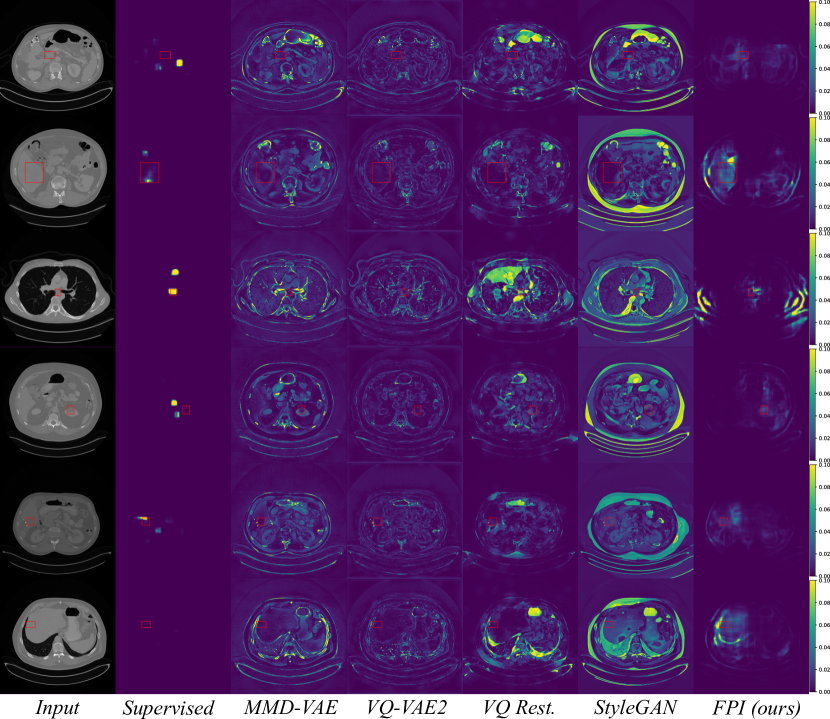

For the DeepLesion dataset, FPI was trained under the continuous (interpolation factor) setting without stochastic weight averaging. The results demonstrate that FPI can identify real medical anomalies despite being trained on only normal images. Table 2 displays both image and pixel level AUROC scores as well as estimated DICE scores. ROC curves are shown in Figure 6.

| Method | Image-level | Pixel-level | |||

| AUROC | AUROC | ||||

| Supervised | 0.554 | 0.923 | 0.226 | ||

| MMD-VAE (Zhao et al. (2019)) | 0.419 | 0.635 | 0.024 | ||

| VQ-VAE2 (Razavi et al. (2019)) | 0.405 | 0.576 | 0.018 | ||

|

0.469 | 0.664 | 0.023 | ||

| StyleGAN (Karras et al. (2019)) | 0.501 | 0.618 | 0.023 | ||

| FPI (ours) | 0.648 | 0.701 | 0.030 | ||

At the image level, the reconstruction-based methods score around 0.5 or below. Several factors contribute toward this, including high variation in normal data, higher reconstruction error from certain structures, and overrepresentation of certain tissue types in the normal test data. Figure 8 shows that reconstruction-based models must learn to reproduce a wide range of structures and different organs. Most of the reconstruction error comes from sharp edges with high contrast and high spatial frequency, i.e., tissue interfaces. Also, the more pixels involved, the higher the contribution to the overall (image-level) anomaly score. As an example, the lungs generally have a high reconstruction error because they span across a large area and contain details with high spatial frequency. The lungs may also be overrepresented in the normal test data. As described in Section 3.1, each anomalous test image is accompanied by parallel slices that give context above and below the anomalous slice. The context slices, minus a margin around the anomalous slice, are used as normal test data, resulting in 116,026 normal test images and 4831 anomalous test images. However, certain regions have more context slices than others. For example, the average number of context slices for an anomalous lung image is 79, whereas soft tissue type lesions (muscle, skin, fat) only have 37 context slices on average. As such, the normal test data may be skewed toward certain organs that have high reconstruction error. This can increase the false positive rate and reduce the area under the ROC curve. This skew may exist in the training data as well, but reproducing details with high spatial frequency can still be challenging for methods that rely on a lower dimensional representation of the data.

The supervised method, which is only trained on slices containing lesions, also performs poorly when tested on images that are both normal and abnormal. This could be fixed by including normal samples during supervised training. But it illustrates that even supervised methods can face difficulty when the test distribution does not match the training distribution. FPI is specifically designed to handle out-of-distribution samples and does not rely on proxy tasks that require full image reconstruction. These properties makes it suitable for detecting subtle lesions within highly variable data.

For the pixel-level score, only slices with lesions are considered so that we can directly assess localization. The supervised method excels in this setting because the training and test data are consistent. Even so, the supervised DICE score is modest and the others are quite low. This can be partly attributed to the fact that bounding boxes are used as approximate segmentation masks. Although the pixel-level anomaly predictions may not overlap accurately with the complete bounding boxes, the AUROC scores indicate that these regions tend to be rated as more anomalous. This level of performance is insufficient for lesion segmentation, but may be reasonable for highlighting suspicious regions in an anomaly setting. All unsupervised methods achieve an AUROC over 0.5 with FPI scoring the highest among the unsupervised methods. Full ROC curves are plotted in Figure 6 (b). Individual ROC curves for each lesion type are also shown for FPI in Figure 7 (a) and for the supervised method in Figure 7 (b). FPI performs similarly on each lesion type, indicating that it is equally sensitive to a broad range of lesions.

Figure 9 displays anomalous examples from the DeepLesion dataset with bounding box labels for each lesion. The outputs from each method show varying levels of sensitivity. MMD-VAE exhibits reconstruction errors throughout the images which reflects the difficulty of learning a compact representation for data with high variation and detail. VQ-VAE2 uses a hierarchical architecture to produce higher fidelity reconstructions with less error. However, this does not help the network to be sensitive to specific irregularities such as lesions. Using the VQ-VAE2 for image restoration can help to highlight regions based on likelihood, rather than purely on intensity differences. This approach can be more selective, but it also tends to highlight certain natural variations that may be deemed less likely. Meanwhile, StyleGAN searches for a normal matching image in its latent space, but it is not always possible to find a good match when the data has complex and detailed structures that can vary greatly across images. In comparison to the reconstruction-based methods, FPI highlights more specific areas in the image that contain lesions or other unusual elements that are not lesions. Finally, the supervised method gives the most lesion-specific activations which can only be learned through labelled examples.